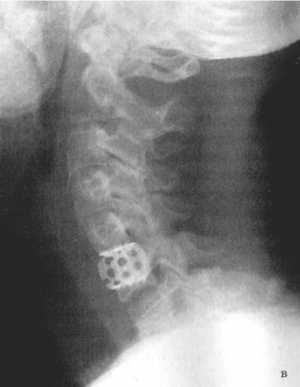

Рис. 3.5: а - травматический вывих С5-С6 позвонков;

б - межтеловая стабилизации металлическим цилиндром сразу после операции;

в - через 3 года после операции. |